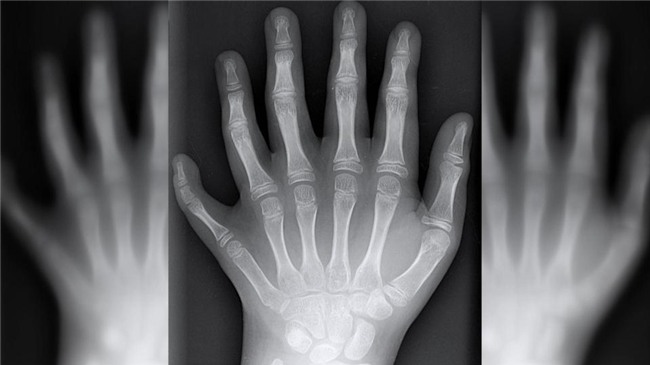

Cậu bé chào đời tên Vinicius, được sinh ra với mỗi bàn tay, bàn chân đều có 6 ngón.

Tình trạng gây ra sự xuất hiện bất thường của gia đình De Silva được gọi là polydactyly. Kì lạ là tình trạng này ảnh hưởng đến khoảng một trong 1000 người. Trong khi đó, cả gia đình dòng họ De Silva có tới 14 người như vậy. Nếu mẹ hoặc cha mang gen gây ra tình trạng polydactyl thì đứa con sinh ra sẽ có 50% khả năng có 6 ngón tay, chân trên 1 bàn như thế.

Cậu bé mới chào đời tên Vinicius, được sinh ra với mỗi bàn tay, bàn chân đều có 6 ngón.

Tiến sĩ Laura Lettice giải thích: "Có rất nhiều đột biến dẫn đến tình trạng này, nhưng đa phần chỉ là có thêm 1 ngón tay hoặc 1 ngón chân. Còn với gia đình De Silva thì họ có tới 2 ngón tay, 2 ngón chân và ở rất nhiều người”.

Tình trạng gây ra sự xuất hiện bất thường của gia đình De Silva được gọi là polydactyly.